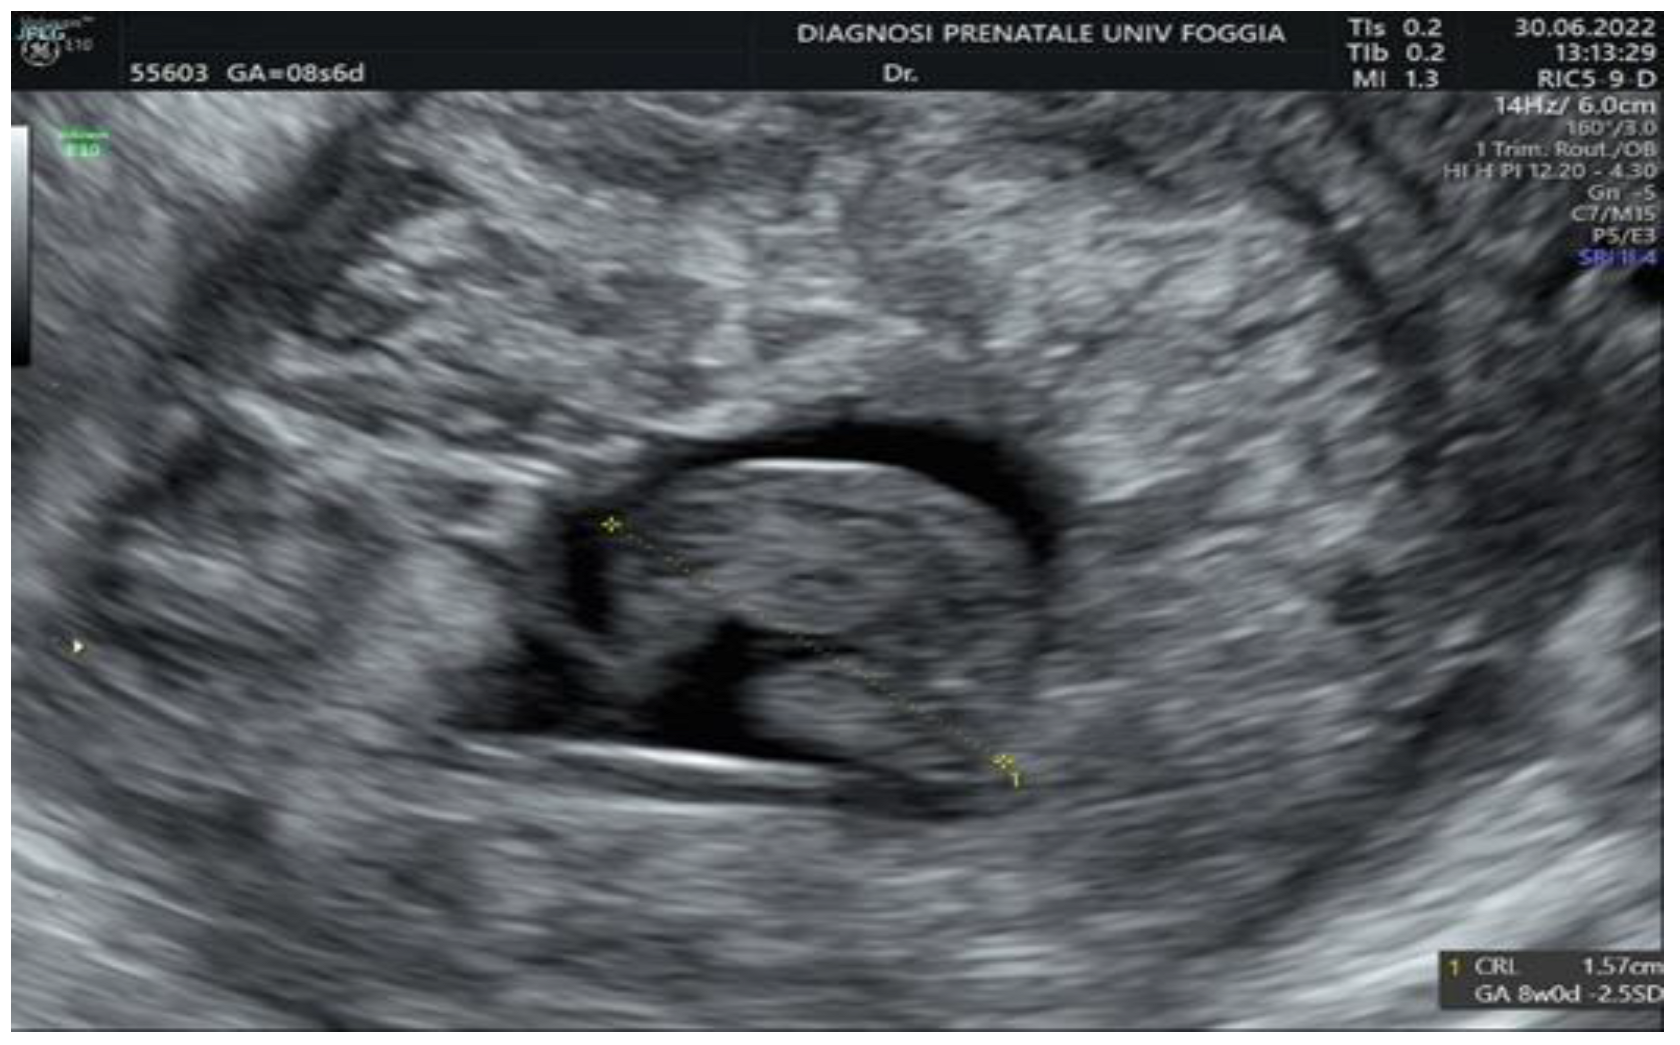

2. Case Presentation